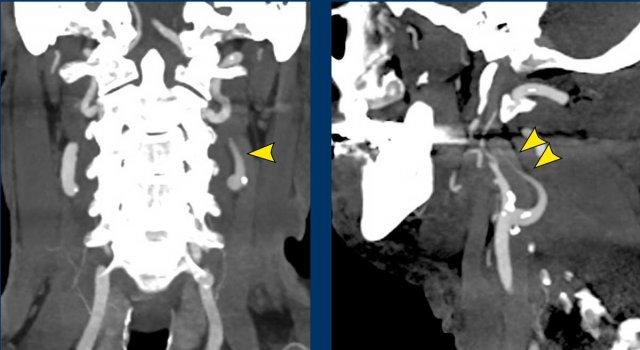

Bệnh nhân nam trẻ tuổi bị tai nạn khi tham gia đua xe mô tô địa hình.

Bệnh nhân được nhập vào khoa ICU với nhiều chấn thương.

Sau ba ngày, bệnh nhân hồi phục ý thức và được ghi nhận có liệt nửa người bên phải, không thể giải thích bằng bất kỳ tổn thương não nào.

Bệnh nhân cũng có hội chứng Horner bên phải.

Hình ảnh

CT lúc nhập viện cho thấy gãy mỏm ngang C7 và gãy xương sườn thứ nhất (đầu mũi tên).

Trên CECT có hiện tượng thoát thuốc cản quang cho thấy đang chảy máu tích cực (vòng tròn).

Continue with the MRI…

Đầu tiên, siêu âm vùng cổ được thực hiện để tìm kiếm tổn thương đứt rễ thần kinh, tuy nhiên việc khảo sát này bị hạn chế do các thay đổi chấn thương ở vùng này.

Sau đó, chụp MRI được thực hiện.

Hình ảnh cắt ngang cho thấy sự tăng cường tín hiệu của các rễ thần kinh, gợi ý tổn thương đám rối thần kinh cánh tay.

Cũng lưu ý tổn thương phần mềm cạnh cột sống bên phải.

Continue….

Ngoài ra, hình ảnh T2W cho thấy một số tín hiệu cao nhẹ trong tủy sống bên phải (mũi tên).

Điều này được xem là bệnh lý tủy sống sau chấn thương và cũng có thể là giải thích cho hội chứng Horner bên phải.